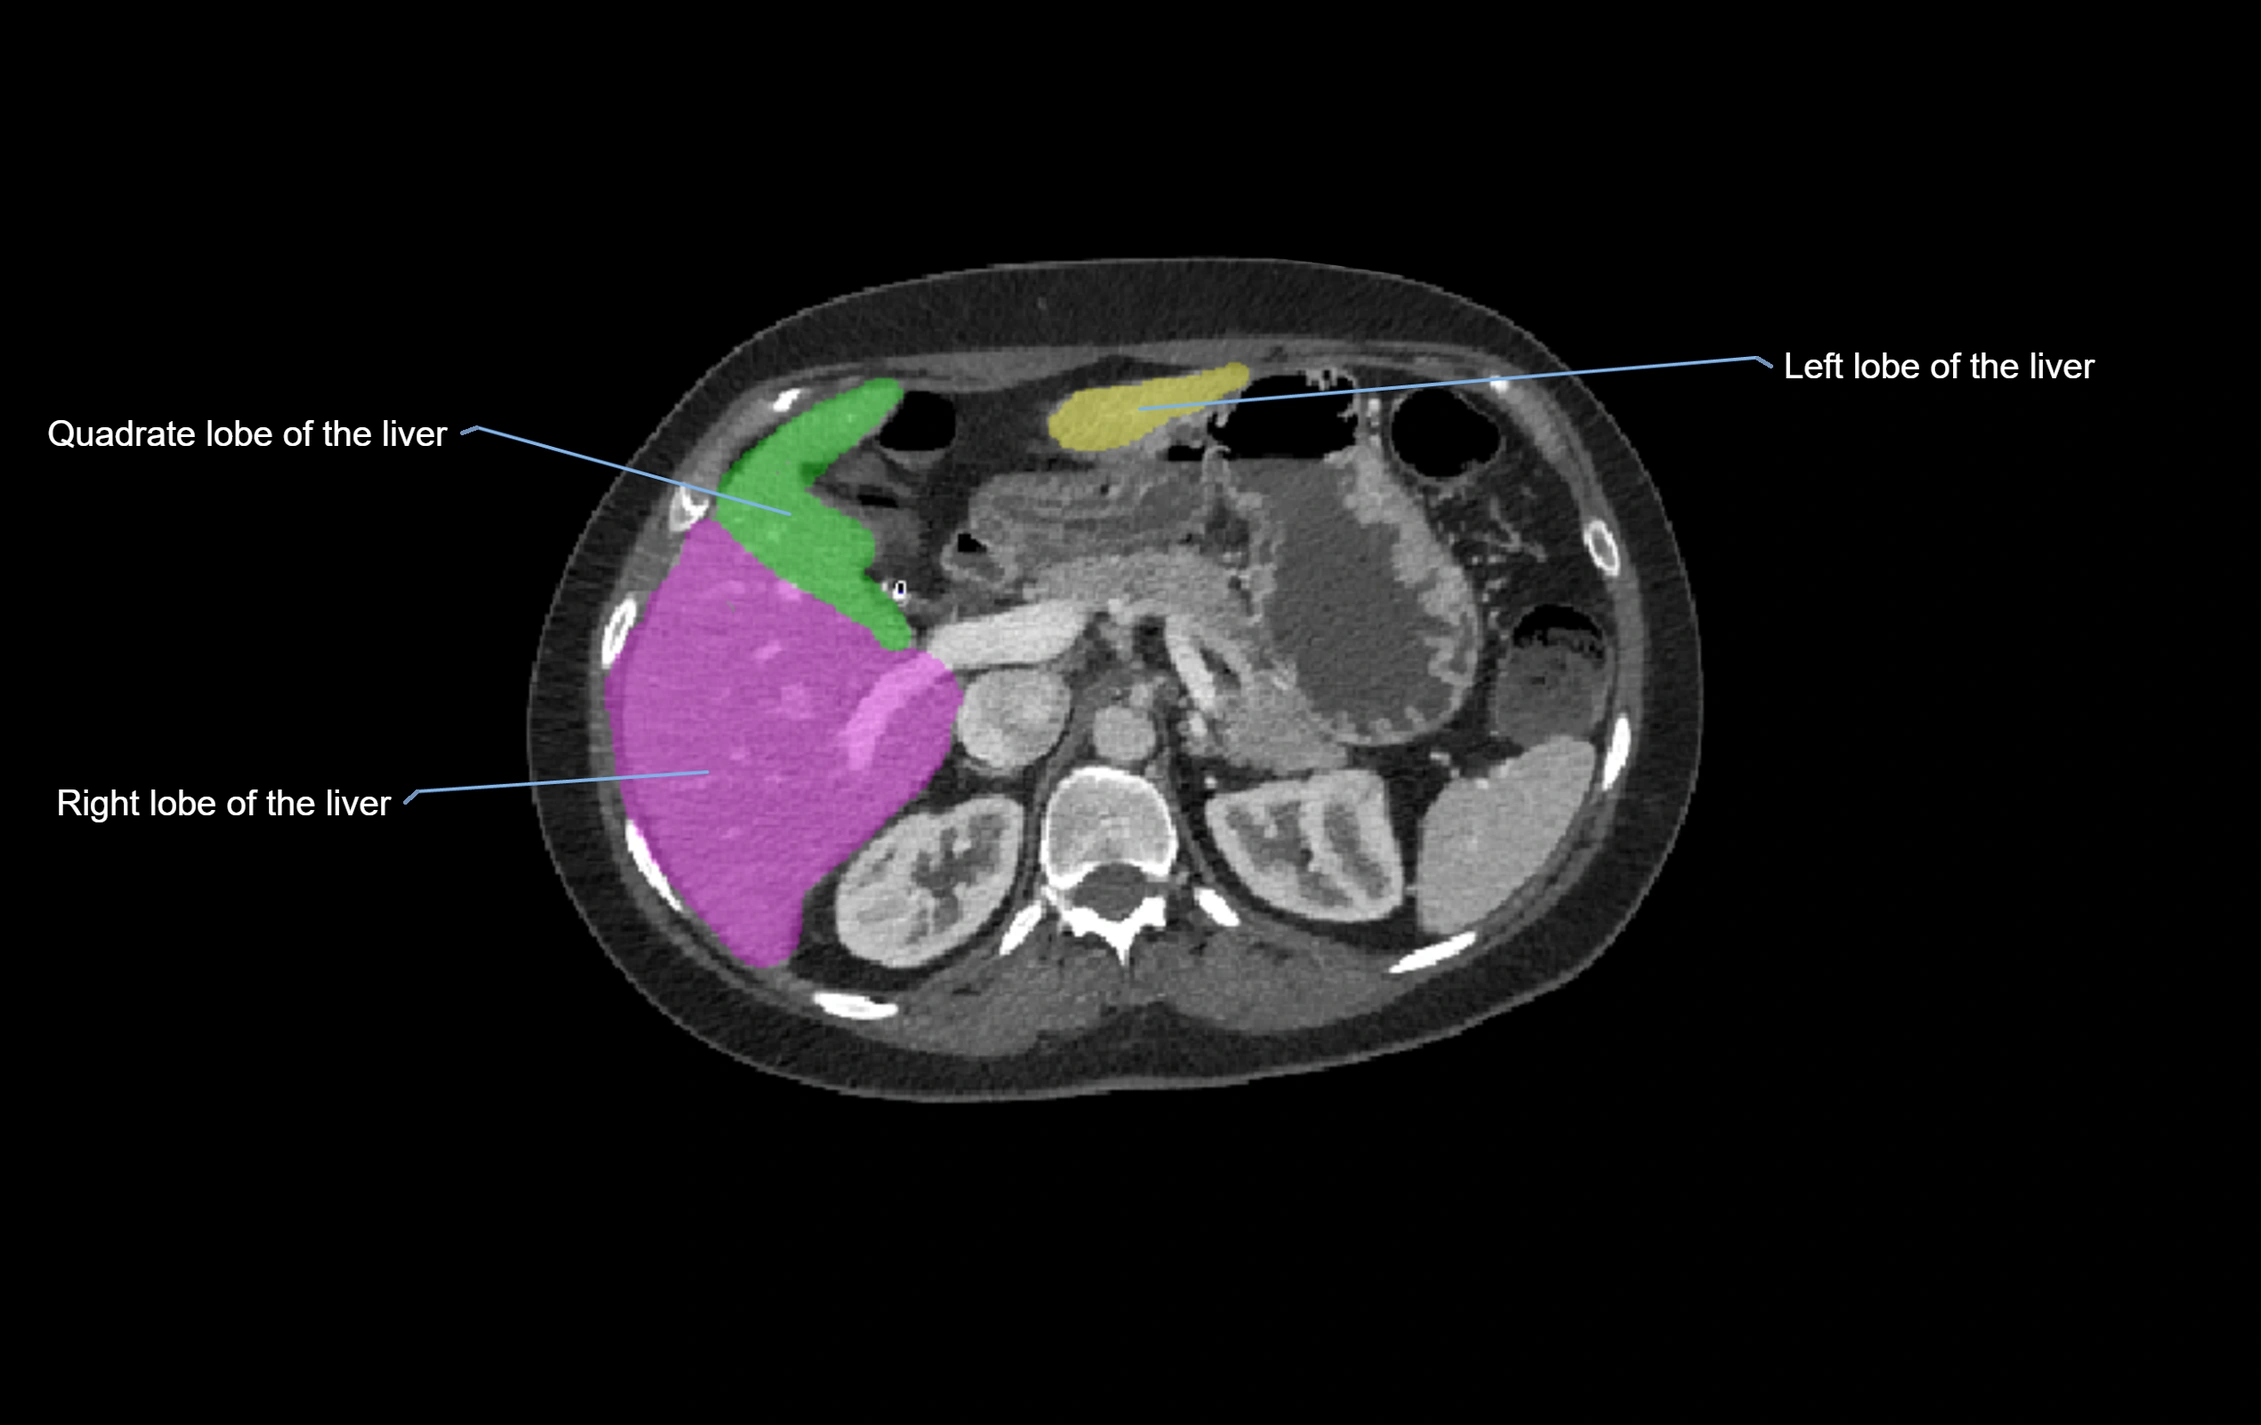

CT Image

image